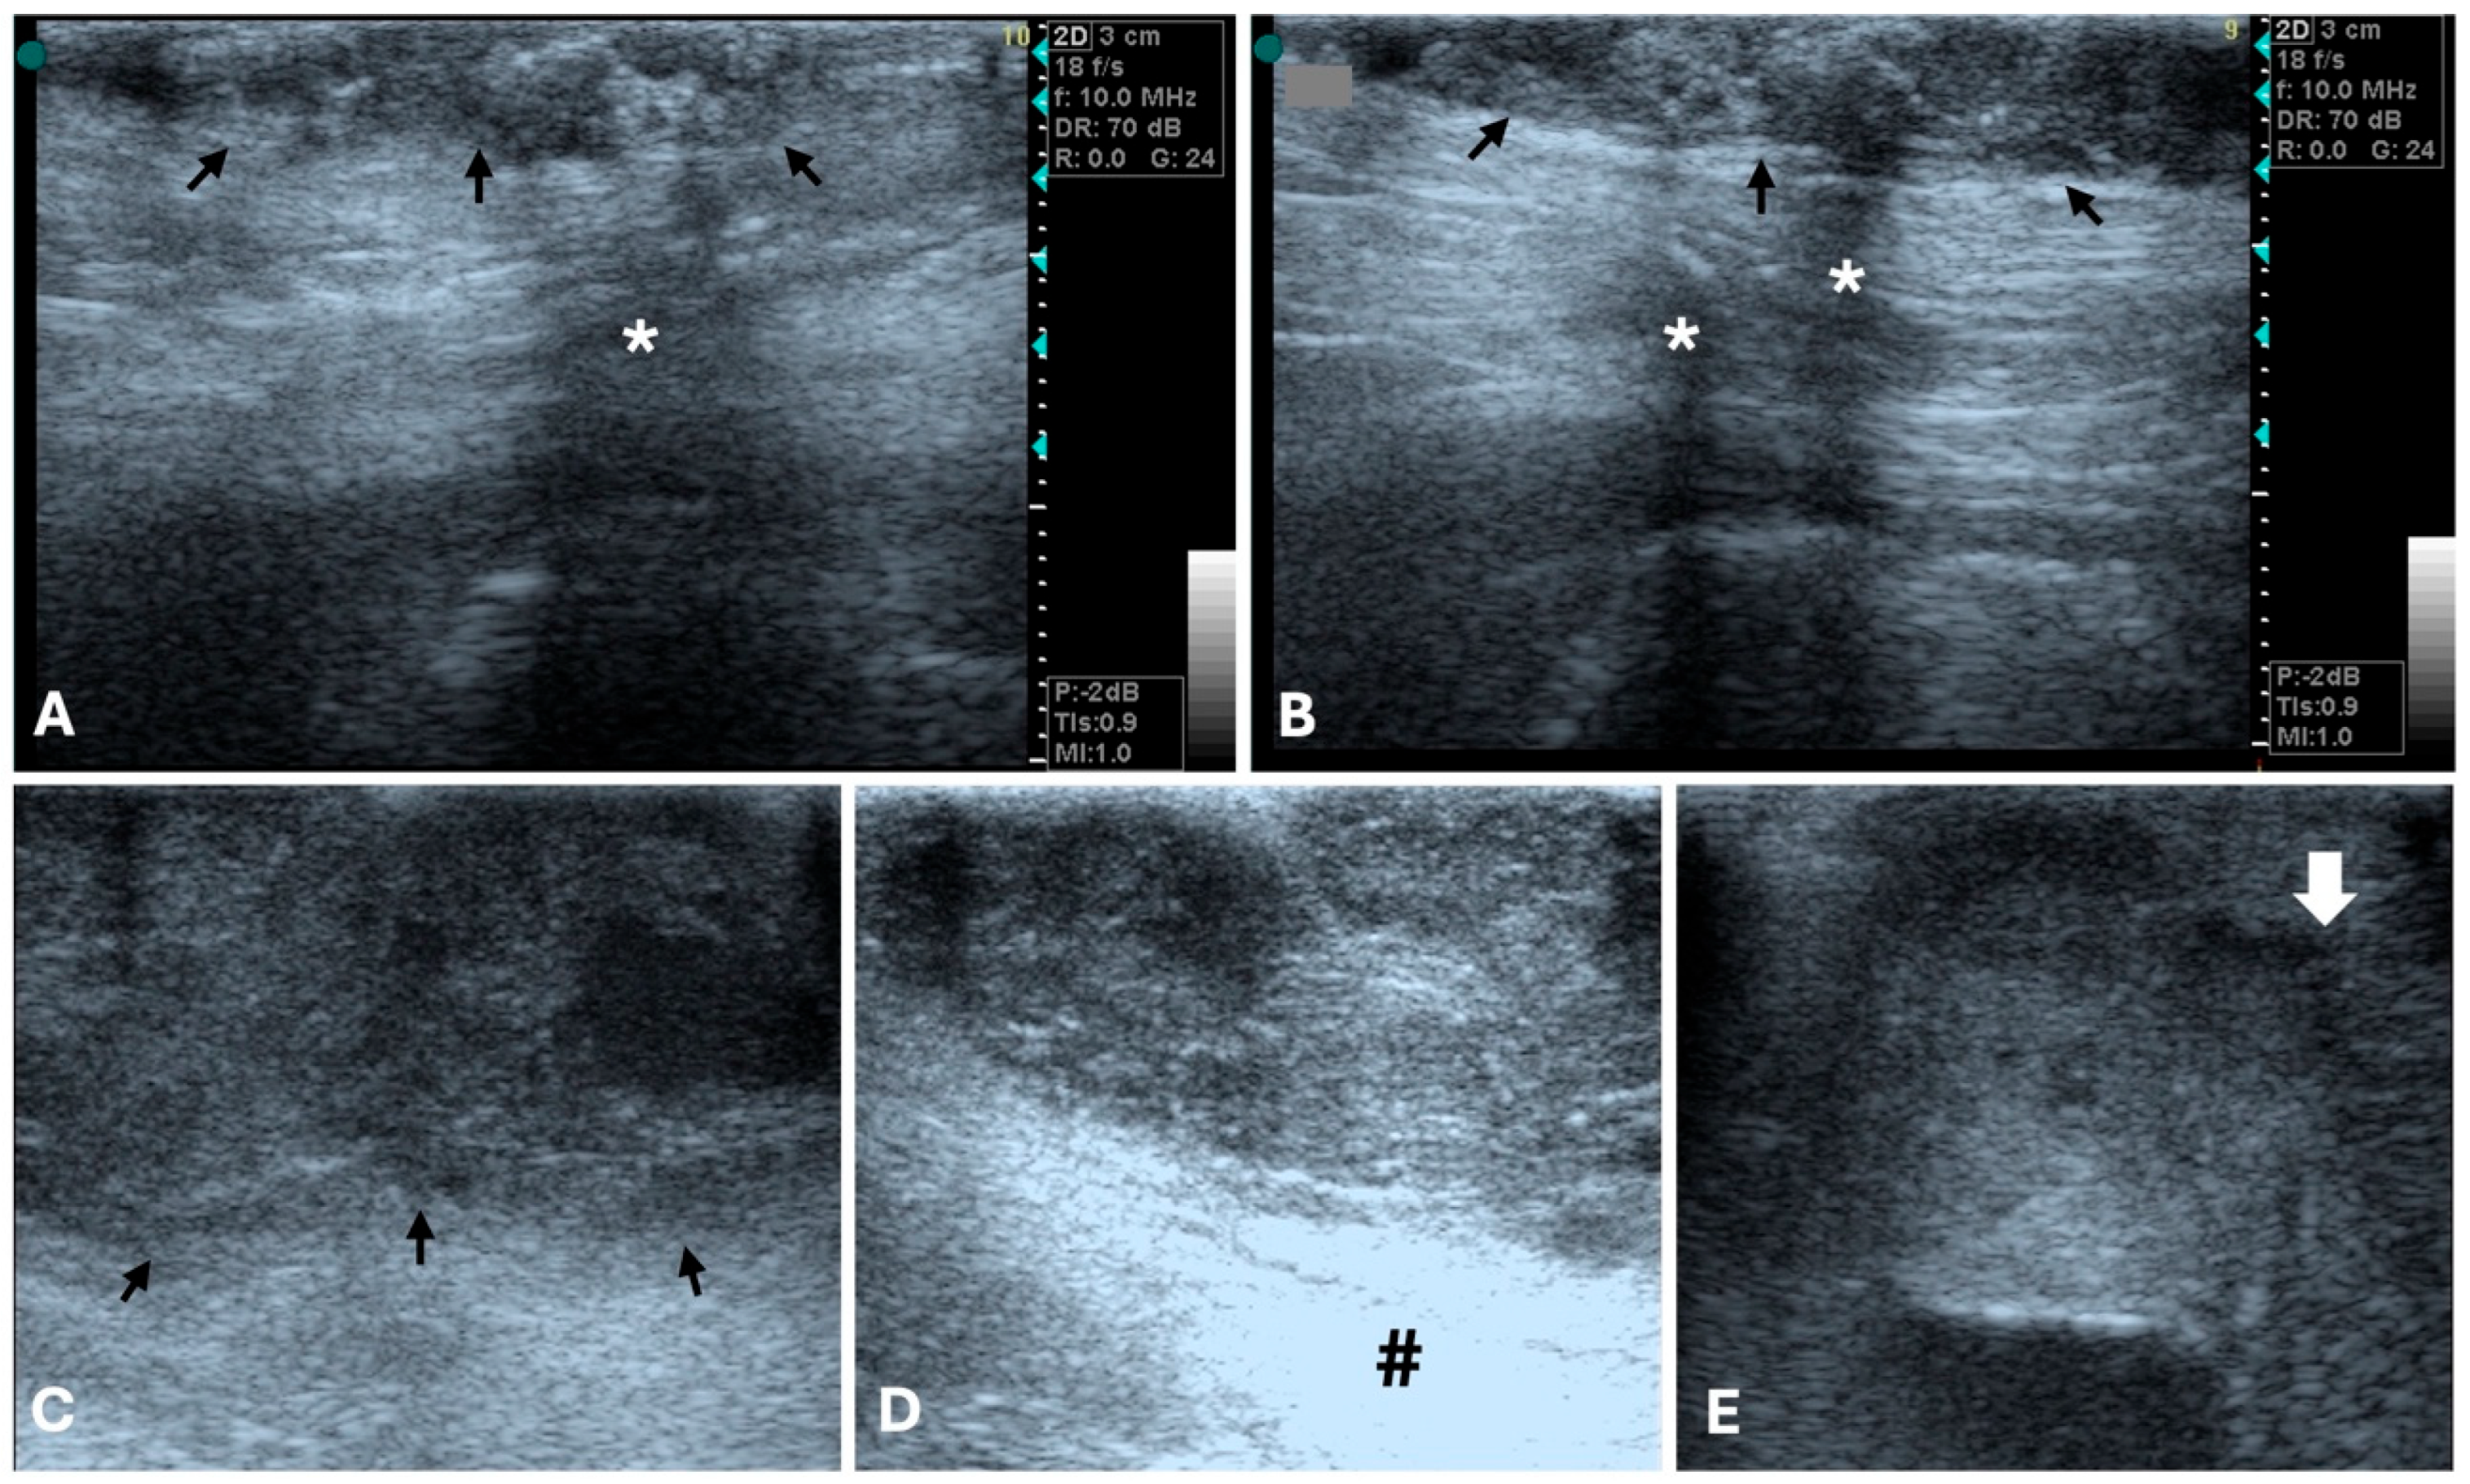

3.1. Ultrasonography

- Feliciano, M.A.R.; Uscategui, R.A.R.; Maronezi, M.C.; Simões, A.P.R.; Silva, P.; Gasser, B.; Pavan, L.; Carvalho, C.F.; Canola, J.C.; Vicente, W.R.R. Ultrasonography Methods for Predicting Malignancy in Canine Mammary Tumors. PLoS ONE 2017, 12, e0178143. [Google Scholar] [CrossRef]

- Vannozzi, I.; Tesi, M.; Zangheri, M.; Innocenti, V.M.; Rota, A.; Citi, S.; Poli, A. B-Mode Ultrasound Examination of Canine Mammary Gland Neoplastic Lesions of Small Size (Diameter < 2 cm). Vet. Res. Commun. 2018, 42, 137–143. [Google Scholar] [CrossRef]

- Feliciano, M.A.R.; Vicente, W.R.R.; Silva, M.A.M. Conventional and Doppler Ultrasound for the Differentiation of Benign and Malignant Canine Mammary Tumours. J. Small Anim. Pract. 2012, 53, 332–337. [Google Scholar] [CrossRef] [PubMed]

- Nyman, H.T.; Nielsen, O.L.; McEvoy, F.J.; Lee, M.H.; Martinussen, T.; Hellmén, E.; Kristensen, A.T. Comparison of B-Mode and Doppler Ultrasonographic Findings with Histologic Features of Benign and Malignant Mammary Tumors in Dogs. Am. J. Vet. Res. 2006, 67, 985–991. [Google Scholar] [CrossRef] [PubMed]

- Gonzalez de Bulnes, A.; Garcia Fernandez, P.; Mayenco Aguirre, A.M.; Sanchez de la Muela, M. Ultrasonographic Imaging of Canine Mammary Tumours. Vet. Rec. 1998, 143, 687–689. [Google Scholar]

- Baştan, A.; Özenc, E.; Pir Yağci, İ.; Baki Acar, D. Ultrasonographic Evaluation of Mammary Tumors in Bitches. Kafkas Univ. Vet. Fak. Derg. 2009, 15, 211–216. [Google Scholar] [CrossRef]

- Marquardt, C.; Burkhardt, E.; Failing, K.; Wehrend, A. Sonographic Examination of Mammary Tumors in Bitches. Part I: Individual Criteria Detectable by Sonography and Their Correlation with Tumor Dignity. Tierärztl. Prax. Kleintiere. 2003, 31, 275–283. [Google Scholar] [CrossRef]

- Soler, M.; Dominguez, E.; Lucas, X.; Novellas, R.; Gomes-Coelho, K.V.; Espada, Y.; Agut, A. Comparison between Ultrasonographic Findings of Benign and Malignant Canine Mammary Gland Tumours Using B-Mode, Colour Doppler, Power Doppler and Spectral Doppler. Res. Vet. Sci. 2016, 107, 141–146. [Google Scholar] [CrossRef]

- Guedes, P.E.B.; Daniel, H.B.T.; Rosa Sampaio, K.M.O.; da Silva, E.B.; Ferreira, M.L.; de Lavor, M.S.L.; de Oliveira Clark, R.M.; Wenceslau, A.A.; Said, R.A.; Silva, F.L. Clinical and Ultrasonographic Aspects of Benign and Malignant Mammary Tumors in Female Dogs. Acta Sci. Vet. 2020, 48, 101276. [Google Scholar] [CrossRef]

- Gasser, B.; Rodriguez, M.G.K.; Uscategui, R.A.R.; Silva, P.A.; Maronezi, M.C.; Pavan, L.; Feliciano, M.A.R.; Vicente, W.R.R. Ultrasonographic Characteristics of Benign Mammary Lesions in Bitches. Vet. Med. 2018, 63, 216–224. [Google Scholar] [CrossRef]